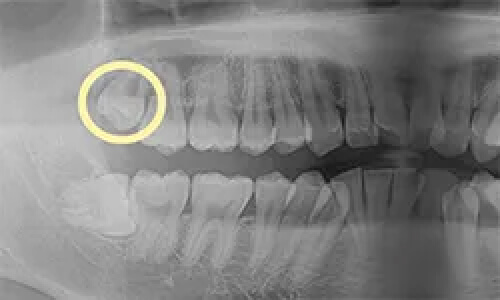

CASE 01

左上の親知らずを抜きたい

親知らずの生え方

斜めに生えている

抜歯時間

約1分

抜歯費用

約3,000円-5,000円